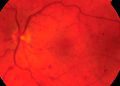

Estudios previos que evalúan la influencia del estado del desprendimiento vítreo posterior (PVD, por sus siglas en inglés) en la oclusión de la vena retiniana central (CRVO, por sus siglas en inglés) sobre la neovascularización retiniana en la CRVO han sugerido que el PVD completo puede ser protector contra la neovascularización en ojos con CRVO isquémica. Un estudio reciente publicado en Retina ha determinado que los casos de CRVO con PVD completo tuvieron una tasa significativamente menor de edema macular cistoide (EMC), menor espesor del subcampo central (ESC) y menor carga de inyección anti-VEGF al año.

El estudio de cohorte longitudinal retrospectivo evaluó a pacientes con diagnóstico agudo de CRVO sin tratamiento previo que tenían al menos 12 meses de seguimiento.1 Se analizaron las características clínicas, los patrones de tratamiento y los resultados entre los ojos estratificados en función de la presencia o ausencia de un PVD completo en la OCT, en el momento de la presentación.

De los 102 casos de CRVO aguda sin tratamiento previo identificados, 52 (el 51%) tenían PVD completo en la presentación y 50 (el 49%) no. El ESC era significativamente menor en aquellos con PVD completo (12 meses: 284,9 µm frente a 426,8 µm; último seguimiento: 278 µm frente a 372,8 µm). La carga de inyección intravítrea de un año era significativamente menor para aquellos que tuvieron un PVD completo que para aquellos que no lo tuvieron (5,1 inyecciones frente a 6,7 inyecciones). A los 12 meses, aquellos con PVD completo en la presentación tuvieron significativamente menos EMC que aquellos con PVD incompleto en la presentación (el 32% frente al 65%).

“Sospechamos que el vítreo puede servir como reservorio y microambiente para las citocinas y moléculas proinflamatorias presentes en ojos con oclusión de la vena retiniana”, escribieron los investigadores en su paper. “La presencia de un PVD completo en ojos con CRVO contribuye para reducir los niveles de moléculas proinflamatorias que circulan localmente en la interfaz vitreomacular, como se ha demostrado en los ojos con retinopatía diabética”.

Llegaron a la conclusión de que “la evaluación de la relación vitreomacular en la OCT en la presentación de los ojos con CRVO puede servir como un biomarcador de imágenes de pronóstico”.